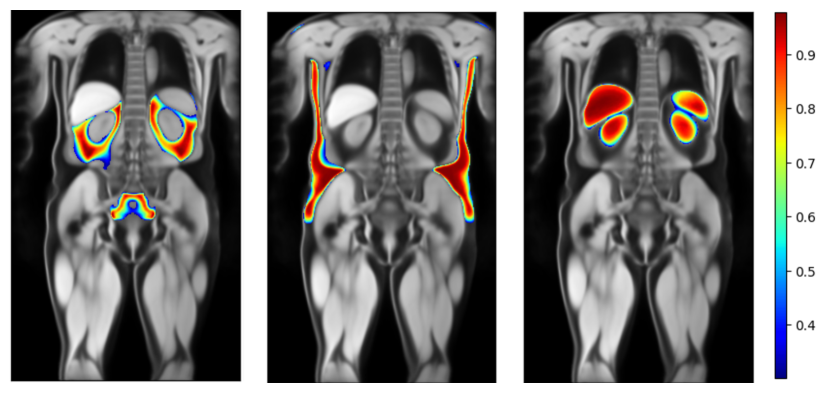

Refer to caption

Figure 4: Example atlas of the overweight male subgroup. We visualise one coronal slice of the unbiased anatomical atlas, overlayed with the probability maps of the abdominal visceral fat (left), the abdominal subcutaneous fat (middle), and the abdominal organs (right)

With this work, we release all six large-scale anatomical atlases for the different population subgroups (based on BMI and sex), as well as the corresponding label atlases of abdominal organs and abdominal fatty tissue. Figure 4 shows an example of these atlases for obese male subjects. As an effort to facilitate research in the area of large-scale body imaging and population studies, we make these atlases publicly available via CERN’s open repository Zenodo, at this address: https://zenodo.org/record/8226039.

The atlas generation pipeline described above is performed for each different subgroup. This results in several atlases for each group: (1) an anatomical atlas, showing the average anatomy, (2) two fatty tissue atlases for abdominal subcutaneous and visceral fat, and (3) one atlas for each abdominal organ (liver, spleen, pancreas, left and right kidney).

The anatomical atlas allows for a general analysis of the whole body regarding overall shape and structure. In contrast, the label atlases (organs and fat) allow for a more focused study of the distribution of specific structures in the body. Figure 4 shows an example of these atlases, overlaying the visceral (left), the subcutaneous fat (middle) and the organ (right) atlases on the anatomical atlas for the male, overweight subgroup. The label atlases can be interpreted as probability maps, indicating the likelihood of finding a certain structure (e.g., the liver) at a specific position in the atlas. A high value in these probability maps indicates a high concentration or a high probability that this area contains a label over the whole population. A low value, on the other hand, suggests the unlikeliness of a specific region to contain the respective label.